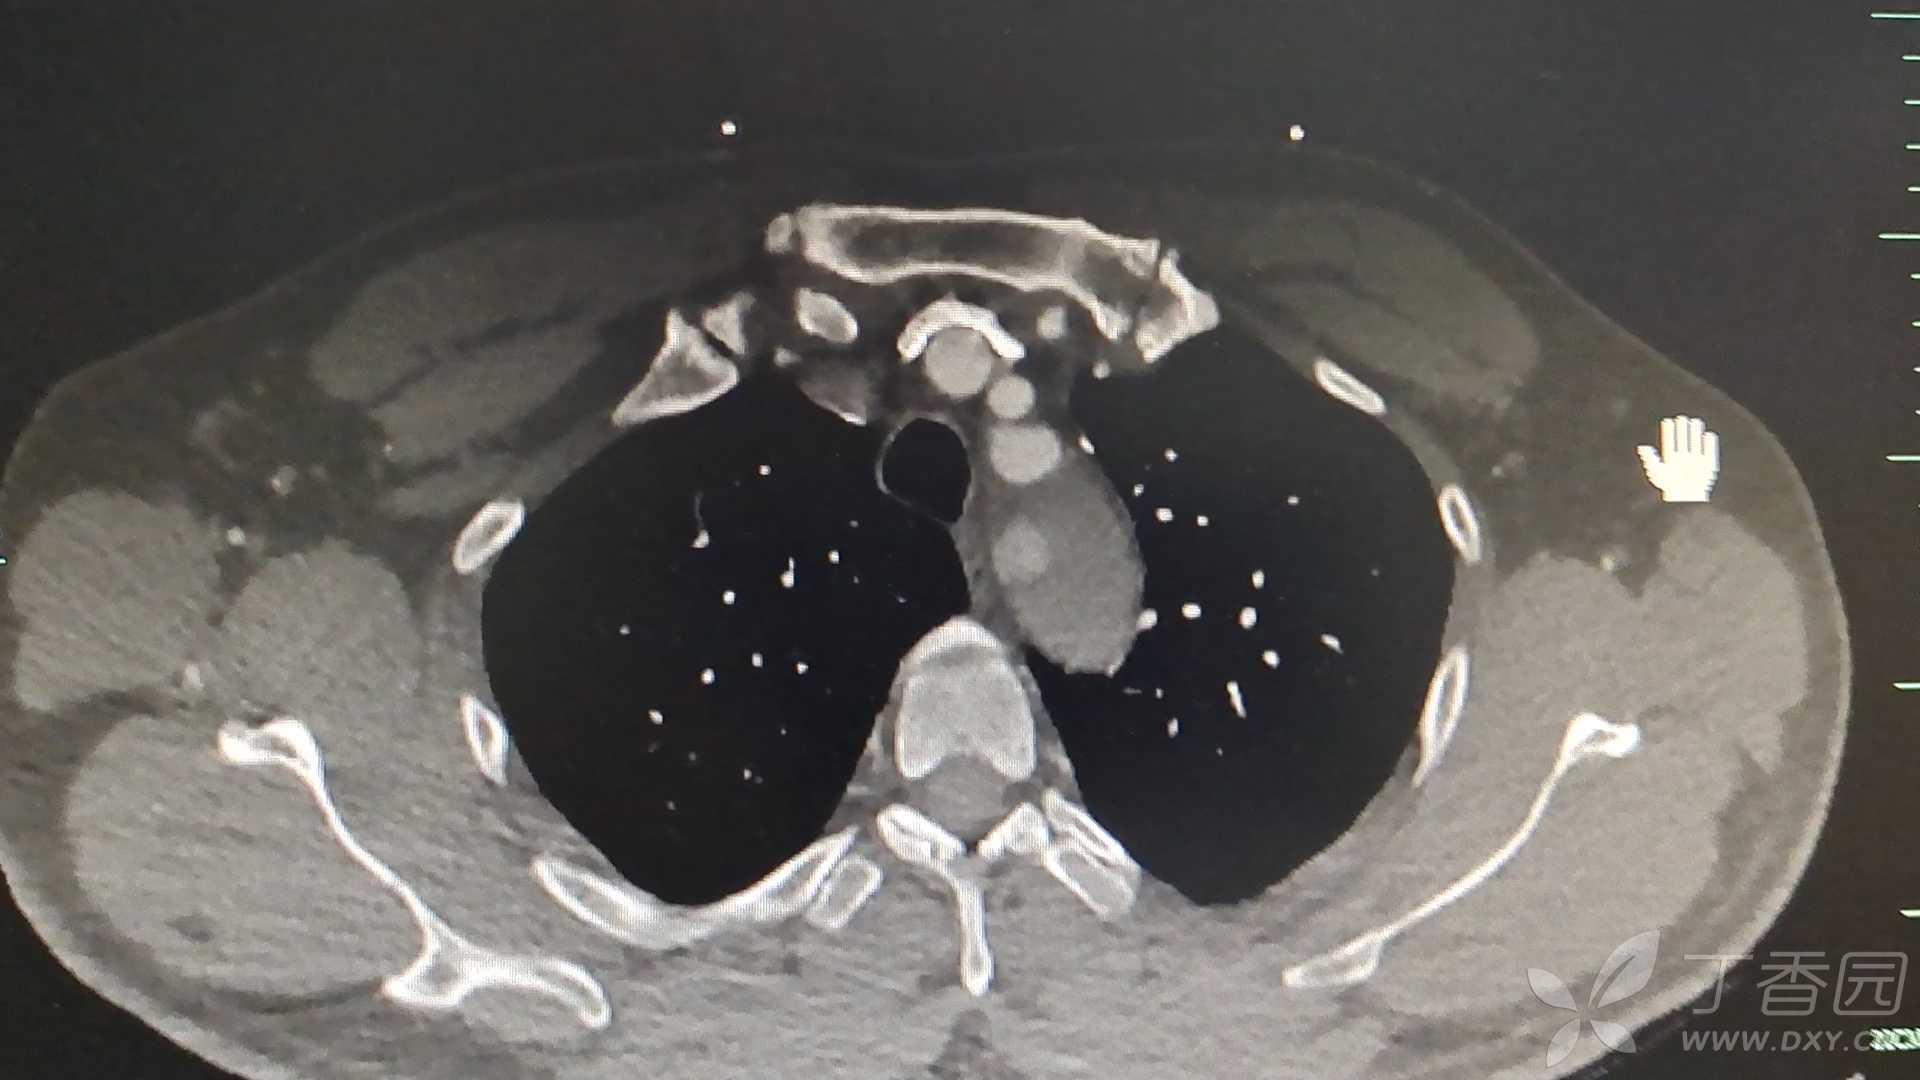

男性,45岁,既往有高血压病史。后背部饱涨不适伴双下肢无力3小时入院。